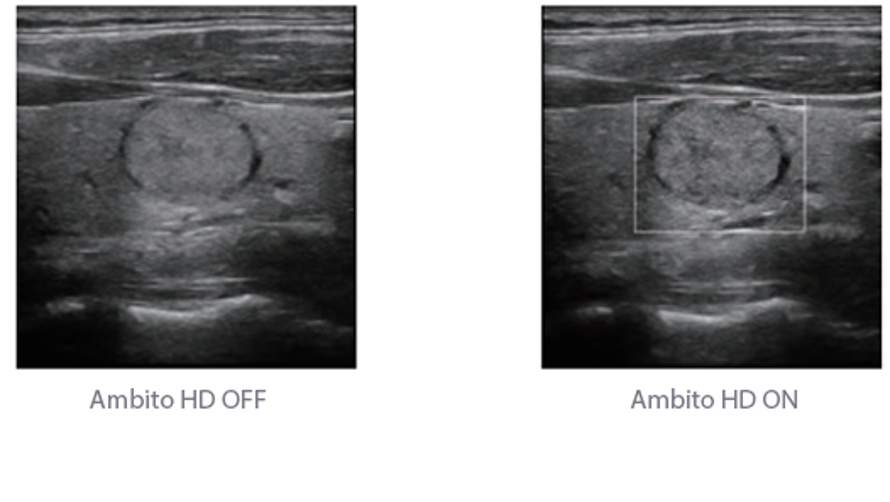

Fin dalla sua fondazione Mindray esplora continuamente nuovi modi per migliorare l'affidabilit├Ā diagnostica. Equipaggiata con la pi├╣ rivoluzionaria tecnologia ZONE Sonography?, la nuova piattaforma ZST+ di Resona 7 porta la qualit├Ā dell'immagine ecografica ad un livello superiore con l'acquisizione per zone e l'elaborazione dei dati canale.

Oltre alla qualit├Ā delle immagini di livello eccellente, Resona 7 migliora anche le capacit├Ā di ricerca clinica il rivoluzionario V Flow per la valutazione emodinamica vascolare, e l'acquisizione piani pi├╣ intelligente dal set di dati 3D per la diagnosi del sistema nervoso centrale fetale. Combinando il pi├╣ intuitivo funzionamento multi-touch basato su gesti e tutte le caratteristiche cliniche essenziali, Resona 7 sta veramente portando nuove tendenze nellŌĆÖinnovazione dellŌĆÖecografia.